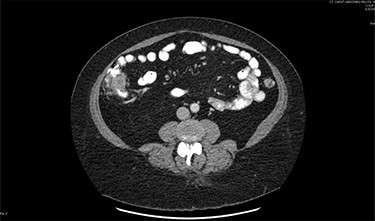

On assessment, the patient denied any symptoms related to her neuroendocrine tumor, including flushing, increased sweating, increased heart rate, wheezing, shortness of breath, diarrhea, weight loss or appetite changes. The only significant family history was a paternal and maternal grandfather with colon cancer. Imaging results were significant for computed tomography (CT) of chest demonstrating very small, but multiple, pulmonary nodules. A CT abdomen and pelvis demonstrated the known neuroendocrine tumor near the ileocecal valve (Fig. 1) as well as two poorly visualized liver lesions (Figs 2–4). The magnetic resonance imaging (MRI) demonstrated two separate one-centimeter lesions in segment 5 and 7 of the liver (Figs 5 and 6). The portal vein lacked normal left and right bifurcation; there was a circumferential right portal vein, which coursed anteriorly and superiorly and ultimately to the left lobe of the liver.